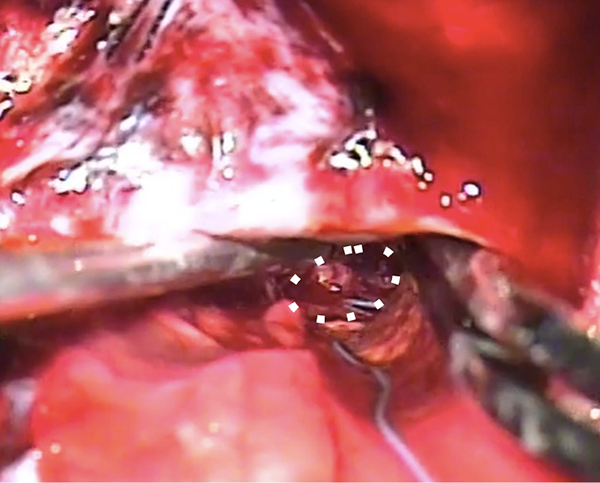

El ingreso al ventrículo se realizó entonces en forma rasante al cuerpo calloso y en su contacto con el cíngulo incidiendo, a diferencia de una callosotomía convencional, unas pocas fibras laterales del CC. El área gliótica post sangrado buscada quedó expuesta de frente al foco del microscopio (Figura 5 B ).

Figura 5B:Estadío intraventricular : Cavernoma, la línea de puntos delimita la lesión.

La cirugía se basó en la disección en 360 grados limitada a la interfase de la lesión con el tejido cerebral, evitando la coagulación (bipolar de ser necesaria) (Figura 5C). En el presente caso, el Cavernoma se encontraba notablemente adherido al parénquima e incluso detectamos dos vasos que retenían la cápsula y podría corresponder a las variantes citoarquitecturales de los Cavernomas descriptos por Awad y cols8.

Figura 5C: Estadío intraventricular: Cavernoma disecado